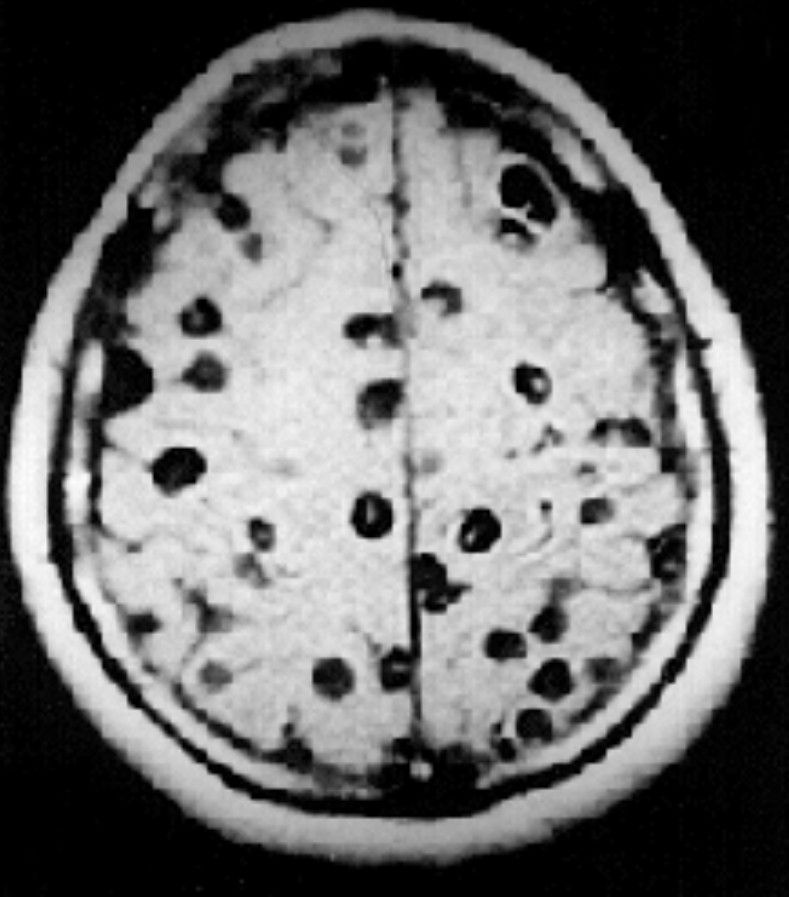

Chẩn đoán sán não thường bao gồm các kiểm tra MRI hoặc CT của não và đôi khi là các xét nghiệm máu. Các xét nghiệm máu có thể không cho kết quả dương tính trong các nhiễm trùng nhẹ. Nếu cần phải phẫu thuật, một bác sĩ bệnh lý sẽ kiểm tra cyst để chẩn đoán.